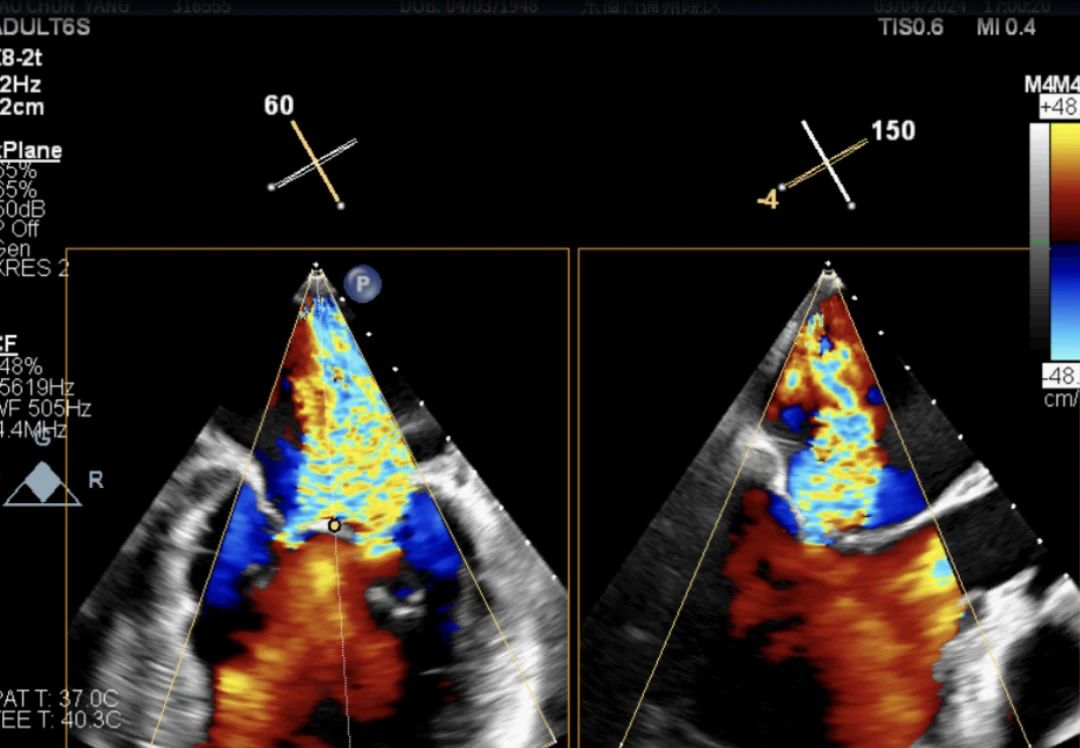

術前經食道超聲提示以P2區為主的二尖瓣中大量反流 術前心臟超聲結果

高質量的TEE圖像對于手術成功至關重要。楊婭主任分析了患者的心臟結構特點,同時聯合醫學影像科主任王寧團隊進行食道實時三維評估,術前充分評估反流量,反流位置,瓣口面積,瓣葉情況。實際發現反流量4+,主要以P2區為主,瓣口面積5.42cm2。